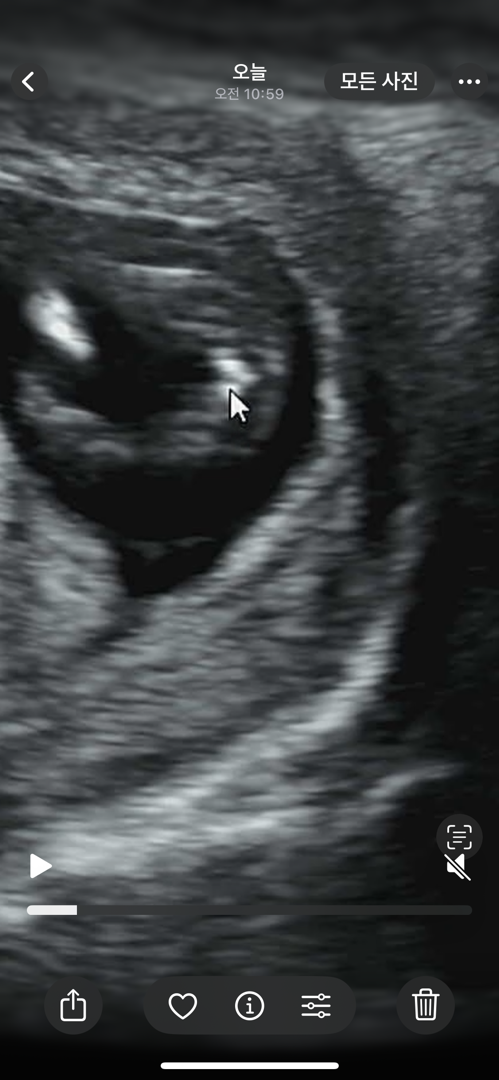

12주5일! 딸이래요🥹❤️

아들 둘에 셋째예용!!!! 사실 성별 기대 안했고! 1차 기형아 검사하고 정밀 초음파에서 스치듯 뭐가 있는걸 봣어요. 정밀 끝나고 진료실 가니까 담당 의사쌤은 제가 이미 아들 둘인것을 알고 계셔서 ㅋㅋㅋㅋ스치듯 뭔가를 봤다니까 내가 한번 봐줄게!! 하셔서 진료실에서 다리 사이 봐주셨어요. 보자마자 딸인데?!!! 이러셨네요!!! 형제맘에서 남매맘이라니...❤️ 주수가 아직 이른감은 있지만 의사쌤이 99프로라시니 믿어보려합니다!!